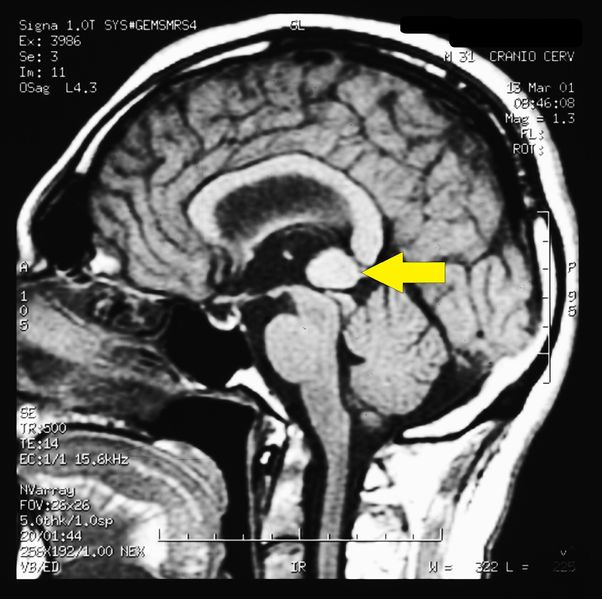

| Description | Brain MR image in bruxist patient affected by Pineal Cavernoma The MR image of the brain performed after intravenous administration of contrast medium in the TSE, FLAIR and GE sequences on the sagittal planes showed the presence of a rounded area of about 1.5 cm in diameter located at the Galeno cistern in a patient with Pineal Cavernoma | ||